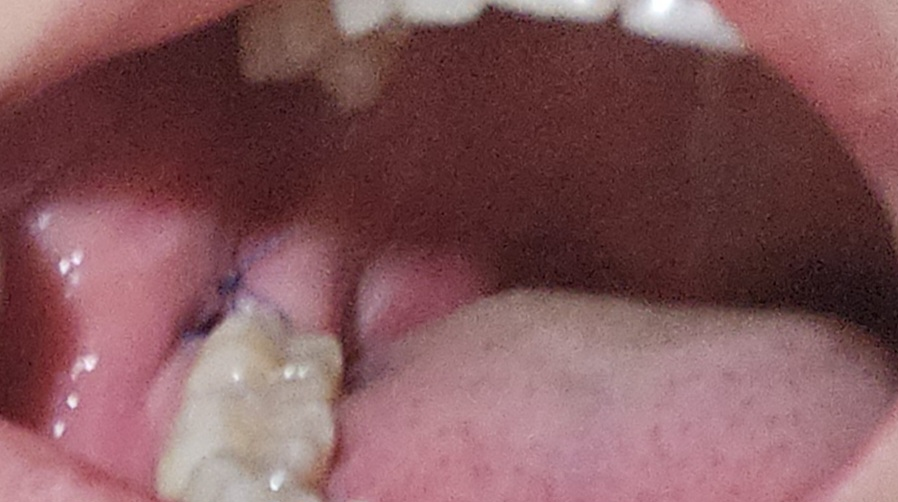

매복사랑니 발치 5일차 하얀게 생겼어요

매복사랑니 발치 후 5일차입니다.

• 3번 째 사진